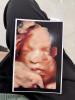

простоо какая же у меня вредная девочка (или скромная 🤣) уже в третий раз пришла на узи, чтоб увидеть ее лицо - опять не показывает, отправили прогуляться и покушать сладкое 🥲

мне так хочется ее увидеть, на втором скрининге тоже из-за тонуса не было видно лица 🥹💔

Походу не суждено мне ее раньше времени увидеть, ну чуть-чуть видела то я

Ни разу у меня не получилось сделать 3д фото 😂, а когда сторисы узистки смотрю, там даже горошинки видно 😂 на 3 скрининге я и гуляла и приседала и покушать шла, ни в какую не показалась, даже положение не поменяла 🤣 и ногами и руками закрылась

На 32 пошла - закрыла руками, через неделю пришла - тонус и плаценту целует еще, сейчас тоже как-то не так лежит, что не видно уже думаю только когда рожу увидимся 😆

Пипиську показала значит, а лицо нет. Значит все таки вредная 😂